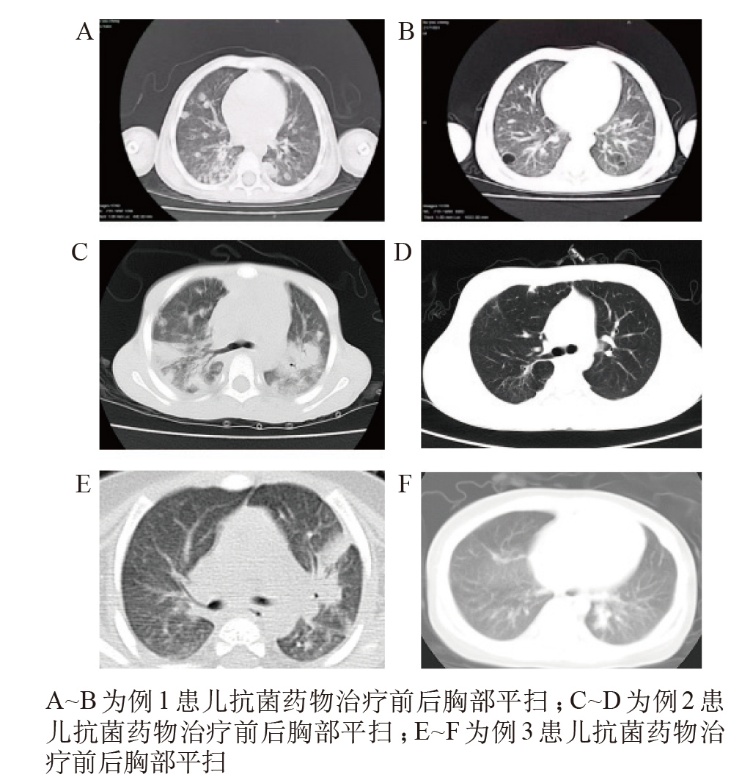

目的 紫色色杆菌(C. violaceum)感染临床表现缺乏特异性,早期识别存在一定难度,儿童患者更为罕见,本文旨在提高临床医师对该病的认识,并丰富全球病例资料。方法 对2012年1月至2021年12月期间收治的4例C. violaceum感染患儿的相关资料进行回顾性分析及报道。结果 4例C. violaceum感染患儿均为男性,系海南省原住民。平均发病年龄(2.50±3.07)岁,发病时间均集中于热带夏季;中位住院时间41.00(12.00~50.16)d,所有患儿均以发热为主要全身症状,3例表现为肺炎合并蜂窝织炎/脓肿形成,1例为肠炎表现,且4例患儿均存在炎症指标升高。病原学诊断通过细菌培养和高通量测序确认。药敏试验显示该菌对碳青霉烯类、氨基糖苷类和喹诺酮类敏感,对青霉素及多数头孢菌素类耐药。随访期间,1例患儿在出院10个月后因脓毒性休克死亡,另1例出现远期复发,提示可能存在慢性隐匿性感染。结论 C. violaceum感染表现形式多样,体液病原学培养对于明确诊断具有至关重要的意义。C. violaceum对青霉素类和头孢菌素类抗生素普遍耐药,药敏试验结果有助于指导治疗,但该疾病存在远期复发及致死风险,临床需提高警惕并加强随访。

Objective Chromobacterium violaceum (C. violaceum) infection presents with non-specific clinical manifestations, posing challenges for early identification—particularly in pediatric populations, where cases are extremely rare. This study aims to enhance clinicians’ awareness of pediatric C. violaceum infection and expand the global repository of case data. Methods A retrospective analysis and report were conducted on the relevant data of 4 children with C. violaceum infection admitted from January 2012 to December 2021. Results All 4 patients were male native residents of Hainan Province. The mean age at onset was (2.50±3.07) years, with all cases occurring during the tropical summer season. The median length of hospital stay was 41.00 (12.00-50.16) days. Fever was the predominant systemic symptom in all patients, 3 cases presented with pneumonia complicated by cellulitis/abscess formation, while 1 case manifested as enteritis. Elevated inflammatory markers were observed in all 4 patients. Etiological diagnosis was confirmed via bacterial culture and high-throughput sequencing. Antimicrobial susceptibility testing demonstrated susceptibility to carbapenems, aminoglycosides, and quinolones, but resistance to penicillins and most cephalosporins. During follow-up, 1 patient died of septic shock 10 months post-discharge, and another experienced late recurrence, suggesting the potential for chronic latent infection. Conclusion C. violaceum infection exhibits diverse clinical presentations. Pathogen culture of body fluids is critical for definitive diagnosis. While C. violaceum is universally resistant to penicillins and cephalosporins, antimicrobial susceptibility testing results are valuable for guiding treatment. Given the risks of late recurrence and mortality, clinicians should maintain vigilance and implement rigorous long-term follow-up for affected pediatric patients.